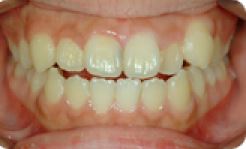

치아교정 세라믹브라켓 전후사례 | 2020.03.06 |